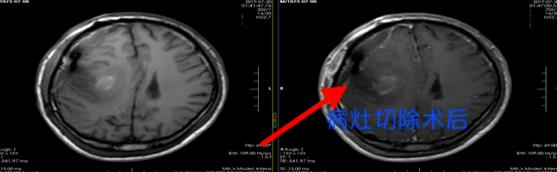

随后,为其实施了右侧额叶中央区占位性病变切除术和寄生虫摘除术。一条长约8厘米的裂头蚴被缓慢地捉了出来。

术后

目前,陆某神志已经恢复清楚,言语答话正常,理解力、记忆力、逻辑思维能力也都和常人无异,头部手术伤口也愈合良好,手脚动作灵敏,即将出院回家。